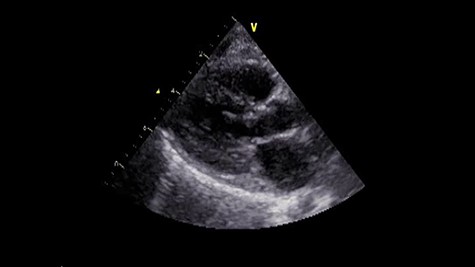

A male infant born at 34-week gestation with 1531-g birth weight was diagnosed with porencephaly based on fetal examination. The patient had persistent hemolytic anemia and jaundice and was diagnosed with a mutation in collagen type IV alpha 1 chain (COL4A1) by postnatal genetic analysis. The details of metabolic and muscular complications of the patient were described in a previous report [2]. The patient underwent surgery for ventriculoperitoneal shunt placement for hydrocephalus and seizure at the age of 3 months and was hospitalized several times for recurrent pneumonia until the age of 2 years, at which time he was diagnosed with LVOTS and moderate MR. The patient was treated with β-blockers for 6 months, but LVOTS and MR gradually worsened and SAM of mitral valve was detected at the age of 2 years and 8 months. At the time, the peak pressure gradient of left ventricular outflow tract (LVOT) was 120 mmHg and the MR was severe (Fig. 1 and Video 1). Surgery was planned for septal myectomy for LVOT with mitral valve repair.

Preoperative echocardiography. The abnormal muscle band in left ventricle and severe SAM of the mitral valve are observed. The anterior leaflet of mitral valve obstructs the LVOT in the systolic phase.

Under general anesthesia, cardiopulmonary bypass was established by ascending aortic and bicaval cannulation. After transverse aortotomy, LVOT was exposed through the aortic valve by retracting the aortic wall. The cardiac muscle hypertrophy with abnormal bundle-like cardiac muscle was observed in the LVOT, including the septal area. The hypertrophied area was scooped up by a nerve hook and cut by scalpel (Fig. 2 and Video 2). Next, the left atrium was incised and the mitral valve was exposed. The edge-to-edge technique with a suture of the A2–P2 area was performed for mitral valve reconstruction. Postoperative recovery was uneventful, and echocardiography revealed improved LVOTS with 1.7-m/s peak velocity and no MR or mitral stenosis (Fig. 3 and Video 3).

Postoperative echocardiography. The abnormal muscle band has disappeared, and the SAM of mitral valve is well controlled.